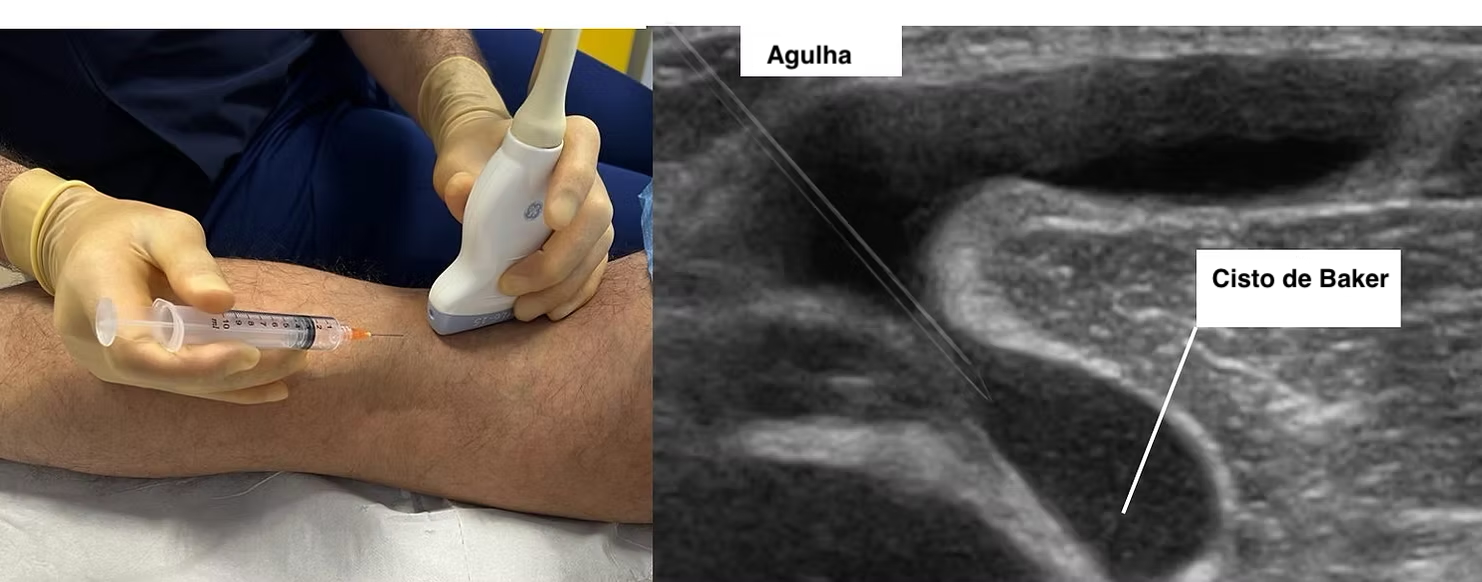

Ultrassonografia

A ultrassonografia é um exame muito útil para confirmar o cisto e avaliar seu conteúdo. Em casos de ruptura, pode demonstrar líquido dissecando os planos da perna. Também é importante para ajudar a afastar trombose venosa profunda.

- aspiração do cisto ou do derrame, em situações específicas.

Em pacientes com artrose e cisto de Baker, medidas conservadoras como aspiração, infiltração e controle da inflamação podem gerar melhora importante dos sintomas, embora parte dos pacientes apresente piora em médio prazo se a doença articular persistir.